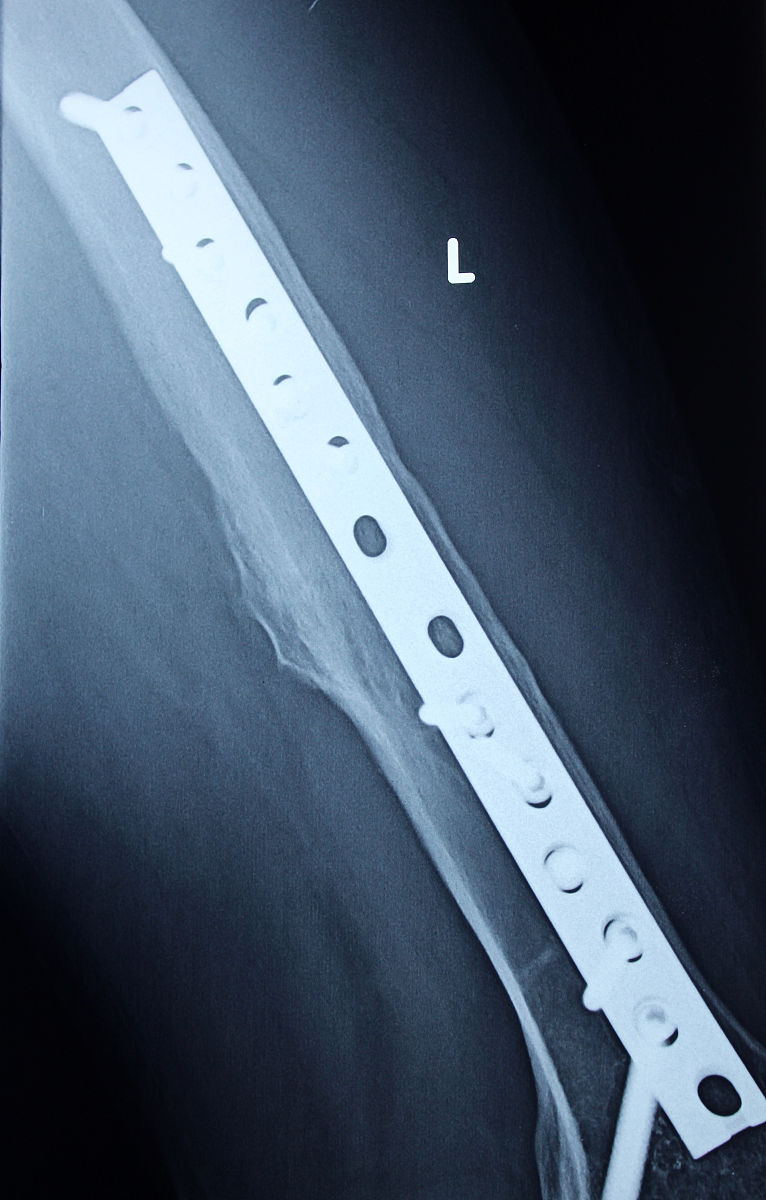

1. 麻醉: 患者接受全身麻醉或局部麻醉。2. 体位: 患者采取仰卧位,患侧髋部外展。3. 切口: 在患侧髋部外侧或前侧做一个切口,用于插入内钉。4. 钻孔: 通过切口使用专用器械在股骨近端钻孔,为插入内钉做好准备。5. 内固定: 将防旋髓内钉插入钻孔,并使用螺钉等固定,确保其稳固地固定住骨折部位。6. X线检查: 术中进行X线检查,确认内钉的位置和固定效果符合预期。7. 伤口处理: 关闭切口,进行伤口缝合和包扎等处理。8. 术后护理: 术后患者需要进行康复训练和物理治疗,以促进骨折愈合并恢复髋关节功能。

• 微创: 相比传统手术,切口更小,对周围组织损伤更小。* 恢复快: 由于创伤小,患者术后疼痛轻,恢复更快,可以更早下床活动。* 固定牢固: 防旋髓内钉能够提供稳定的内固定,有利于骨折愈合。* 并发症少: 与其他手术方式相比,该手术并发症发生率相对较低。

• 尽管该手术风险较低,但仍可能出现感染、出血、神经损伤等并发症。* 部分患者术后可能出现内固定松动、断裂等问题,需要进行二次手术。